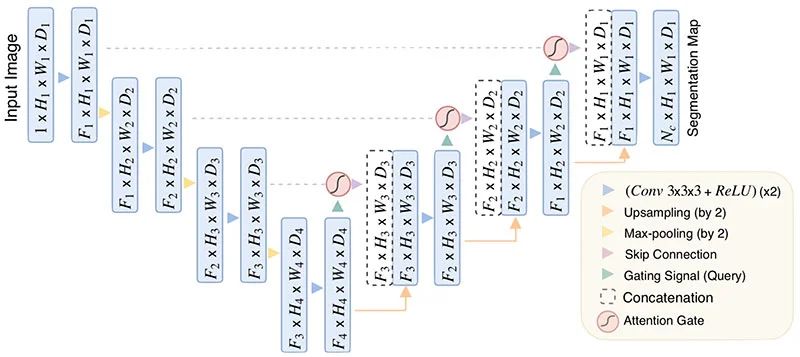

2. 요추 분할 모델 및 디스크 높이 측정 알고리즘

- 모델 학습

- 기존에 널리 이용되는 Segmentation 모델인 U-net architecture를 기반으로 하며, 모델의 Feature 를 찾기 위해 데이터를 다운 샘플링 할때 Crop 및 복사를 해둔 데이터에 Attention Gate 를 적용한 모델.

- 전체 데이터의 20%를 Test에 사용하고, 남은 80%를 10배수 Augmentation 하고, 그 중 60%를 학습에 사용

[사용된 Attention U-Net 아키텍처]

2. 요추 분할 모델 및 디스크 높이 측정 알고리즘 학습(Training) 검증(Validation) 시험(Test) 개요 – Attention U-net 사용 – 학습도중 모델의 성능 평가

– Dice Coefficient Loss 등– 학습 이후 모델의 성능평가

– Dice Coefficient Score 등데이터 비율 23776장 5944장 746장 - Predict 결과물의 각도와 거리 측정